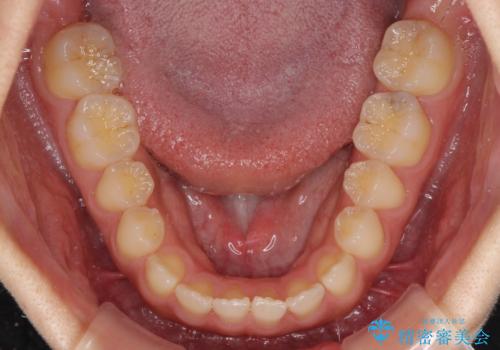

- 後戻りによる上下前歯の隙間を気にして来院された患者様です。

歯列不正はそれほど大きくなかったため、インビザライン・ライトを用いて矯正治療を行うこととしました。

無理のないペースで治療を進め、9ヶ月で終えることができました。